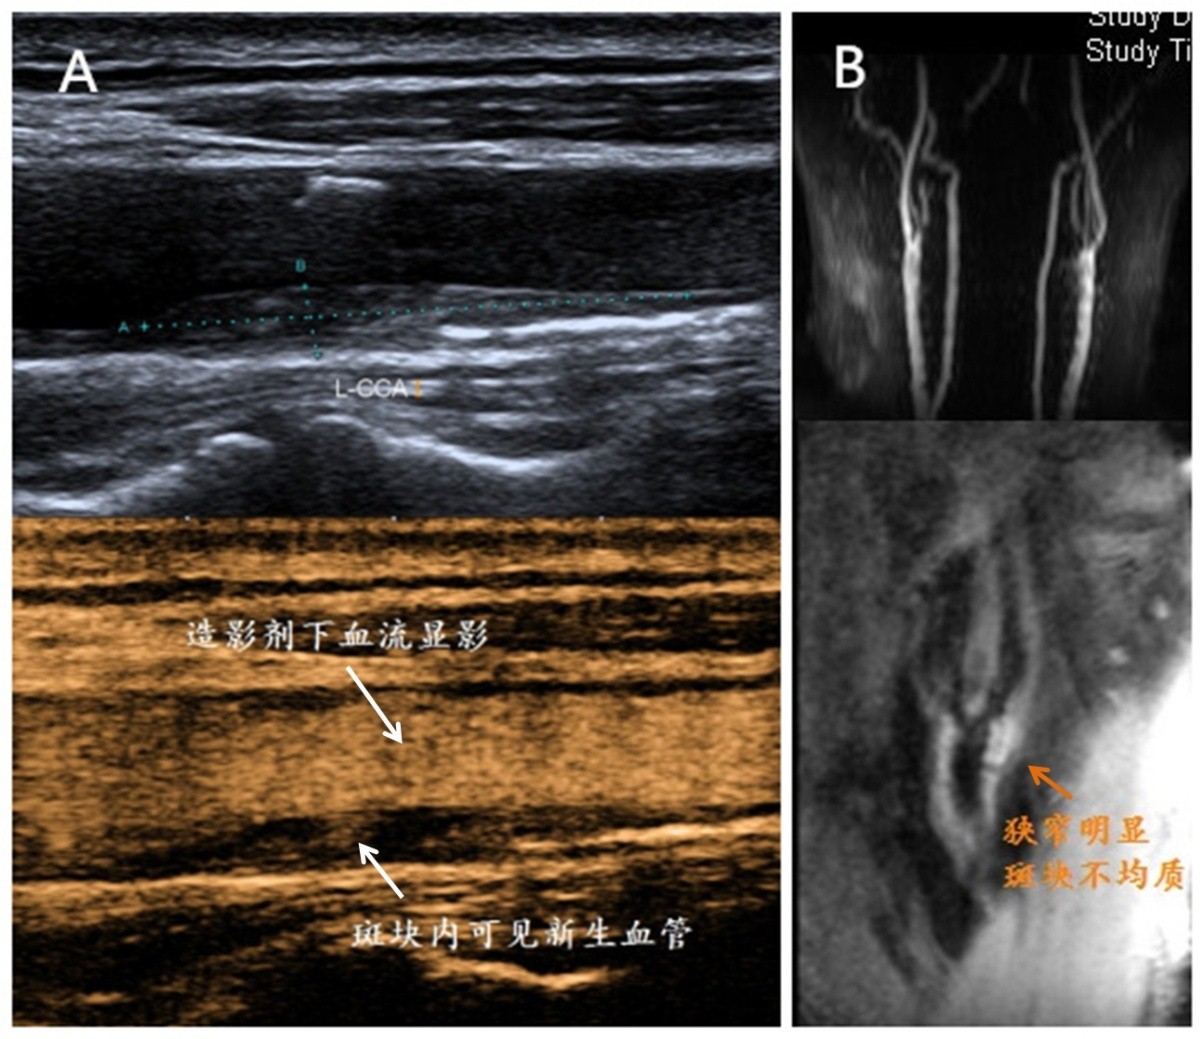

图2 超声造影(A)与磁共振斑块分析(B)均能有效评估颈动脉斑块稳定性

由于颈动脉重度狭窄非常危险,发生脑中风几率高,江伯伯被立刻收进血管外科病房。北京清华长庚医院具备多种先进设备用于全面评估动脉硬化斑块的稳定性,入院后完善斑块评估,颈动脉斑块超声造影检查及磁共振斑块分析均提示,斑块为不稳定斑块,斑块内新生血管形成。不稳定斑块又称易损斑块、“罪犯”斑块,容易破损或脱落造成脑血管梗阻或是继发血栓形成,引起脑梗塞,是斑块中的极坏分子,是必须处理的健康威胁。超声造影技术通过在血管内注射特殊显影剂,图像分辨率得到提升,不稳定斑块内的出血与新生血管能够更容易被探查发现。磁共振斑块分析借助高分辨MRI分析技术,无需注射造影剂,无创评估斑块稳定性。目前北京清华长庚医院超声科、放射科已安排专人开展这2项新技术。